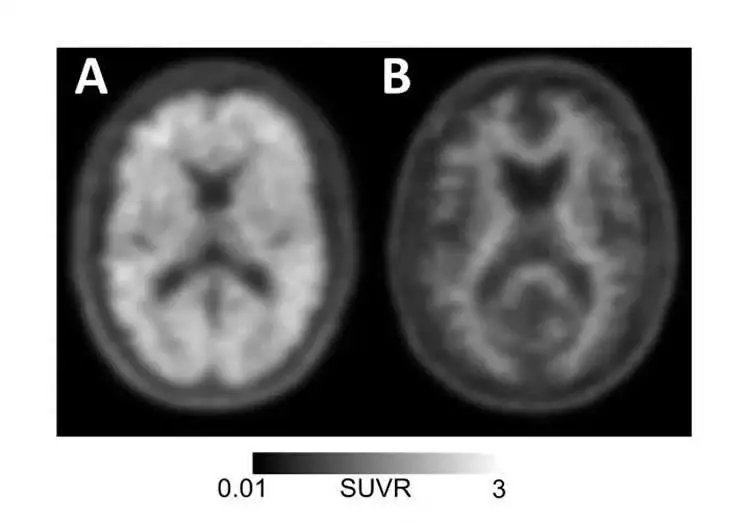

JAMA重大喜报:PET成像或许可以给AD诊断和治疗带来曙光

淀粉样蛋白阳性(左)和淀粉样蛋白阴性(右)PET扫描可分别用于诊断或排除记忆丧失或认知能力下降患者的 2019年4月2日,美国医学会杂志( Journal of the American Medical Association,JAMA)上发表了一项涉及11,000名医疗保险受益人的多中心研究。研究发现,一种检测阿 [...]